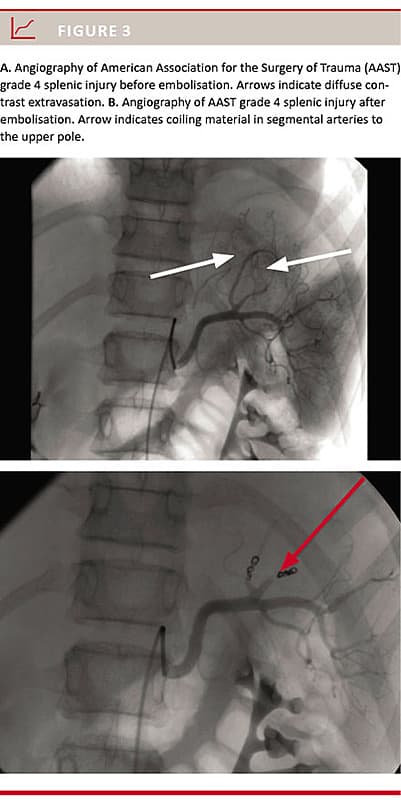

All 34 patients were scheduled for NOM. Two (5.9%) patients later needed surgical intervention. One patient (AAST grade 5 on initial CT evaluation and grade 4 on CT re-evaluation) had a splenectomy performed due to impaired circulation within the first 24 hours, and the other had a laparotomy with suturing of the small intestines due to perforation (AAST grade 1 on initial CT evaluation and grade 2 on CT re-evaluation). During the course of NOM, two (5.9%) patients underwent SAE, one due to diffuse bleeding and one due to a pseudo-aneurism (Figure 2 and Figure 3, respectively). Subsequently, all patients were considered circulatorily stable. Thus, the NOM success rate was 88% (95% CI: 73-97%) without SAE and 94% (95% CI: 80-99%) with SAE.